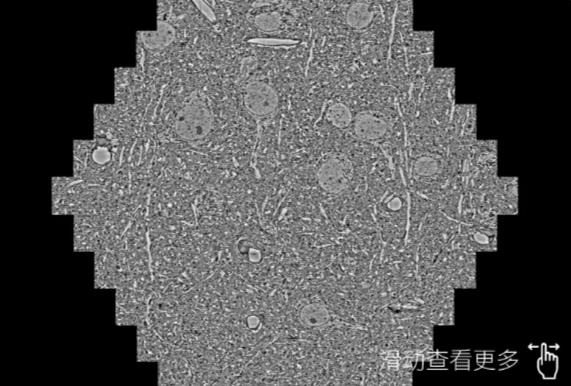

鼠脑切片。左图使用龙潭蔡司龙潭扫描电镜MultiSEM706对165μmx143pm面积区域成像,耗时仅需1.5秒。右图为鼠脑切片中30μm区域放大效果。样品由芝加哥大学B.Kasthuri提供。